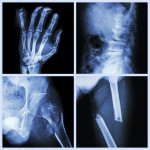

Osteoporosis (which means “porous bone”) is a loss of bone mass and is the most common bone disease. In this condition, holes (lacunas) develop in the bone because newly formed bone tissue cannot fill in the holes. As it progresses, this weaker bone structure can cause the bones to become fragile and, as a result, increase the risk of fractures.

Over 10 million Americans live with it, and 3 out of 4 of them are women. It causes over 1.5 million bone fractures each year, mostly in the joints, spine, hips and wrists.

Symptoms of osteoporosis may not appear before a fracture happens. If they do, they may include joint pain and tenderness, backache, feeling of weakness and loss of height. After a fracture, the pain may be much more severe. The only way to know you have this condition is to get tested for it. Dental x-rays sometimes show bone loss, which may mean osteoporosis has occurred in other body parts.

Bone mineral density (BMD) tests are the only way to detect osteoporosis. These tests are painless and noninvasive, and several tests area available: central machines that measure BMD in the hip, wrist, spine, or total body; and peripheral machines that measure it in the finger, hand, forearm, heel, or shin bone.

The most widely used and best understood test is called DEXA, or Dual Energy X-ray Absorptiometry. DEXA measures BMD of the spine, hip, or total body, and can detect as little as 2% of bone loss per year. DEXA uses about a tenth of the radiation of a chest x-ray. To conduct this test, the patient rests on a padded table. A large mechanical arm moves over the body, with a total body scan taking about 20 minutes to complete.